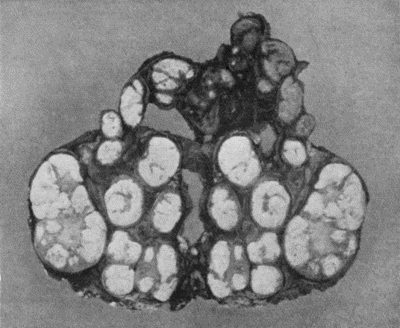

| 114. | Section through Gouty Bursa | 428 |